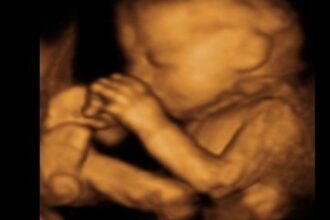

38. HAFTADA BEBEĞİN DEĞİŞİM SEYRİ?

38. haftada bebeğin kafası ve vücut yapısı aynı ayardadır. Yağ depolama yavaşladığı zaman kilo alımı da yavaşlar. Anne karnındaki bebeğin üzerinde bulunan tüyler “laguno” ve peynire benzeyen bir tabaka “vernix caseosa” ortadan kaybolur. Bu iki reaksiyon bebek tarafından yutulur ve doğumdan sonra bağırsak hareketi ile dışarı atılan siyah renkli dışkıdır. Buna da “mekonyum” denir.